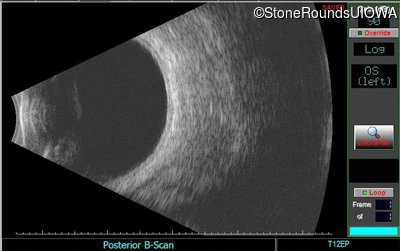

This 41 year old man first came to medical attention at age 18 months when exotropia and amblyopia of his right eye were discovered. At age 11 vitreous strands and retinal vascular sheathing were seen. He has had poor night vision and constricted visual fields since his late teens. Later, at age 44 a traction retinal detachment was noted in his left eye and was treated with a scleral buckle.

Age at visit: 41 years